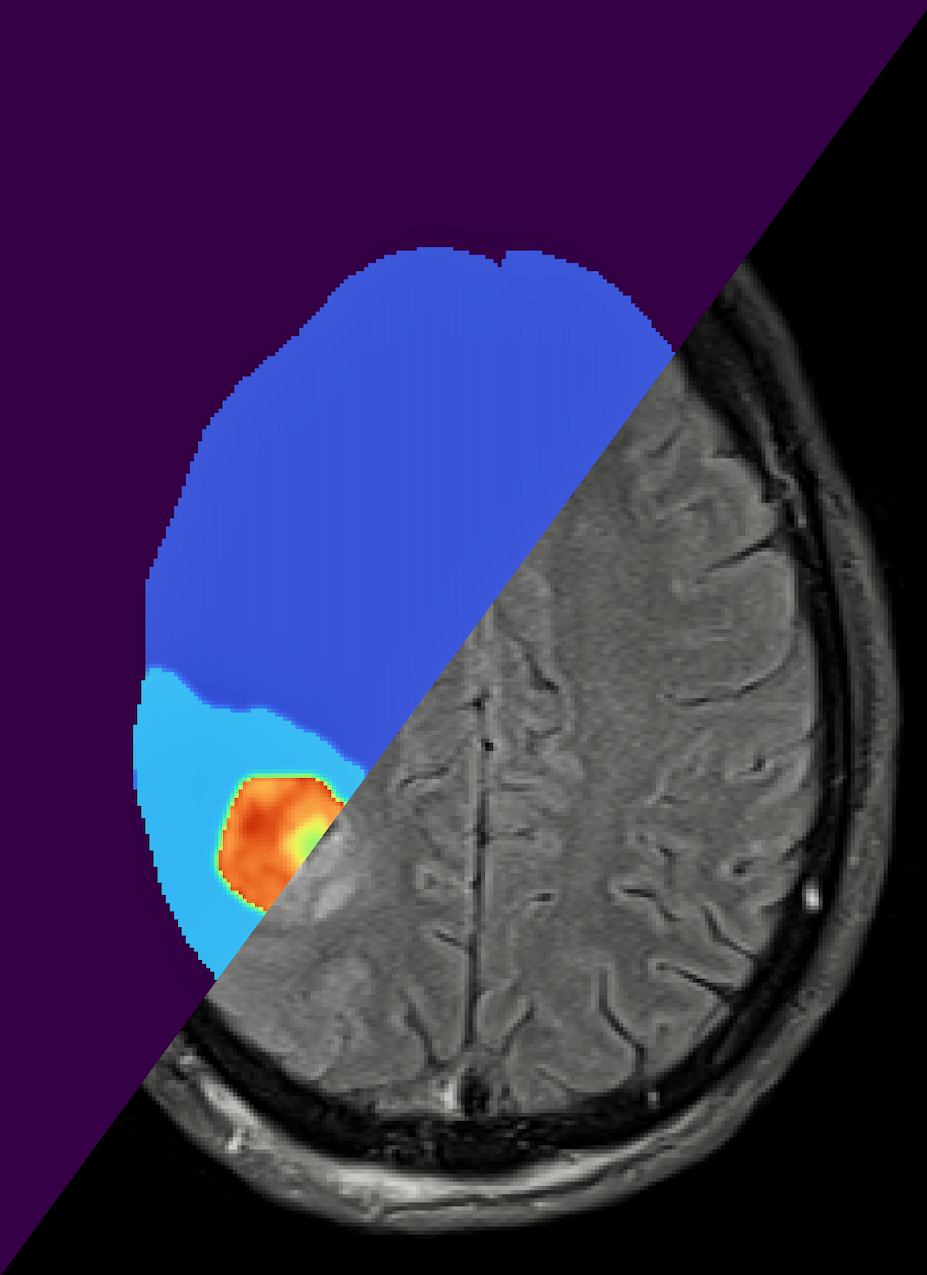

Their funded projects span brain-inspired ionic computing, climate and ocean modeling, patient-specific digital twins for metastatic prostate cancer, and scientific machine learning.

After more than a decade of advances in AI, mathematics and supercomputing, UT is shaping the future of digital twins — bringing together researchers across campus to deploy physics‑informed, AI‑powered models for energy, healthcare, national security and natural hazard mitigation.